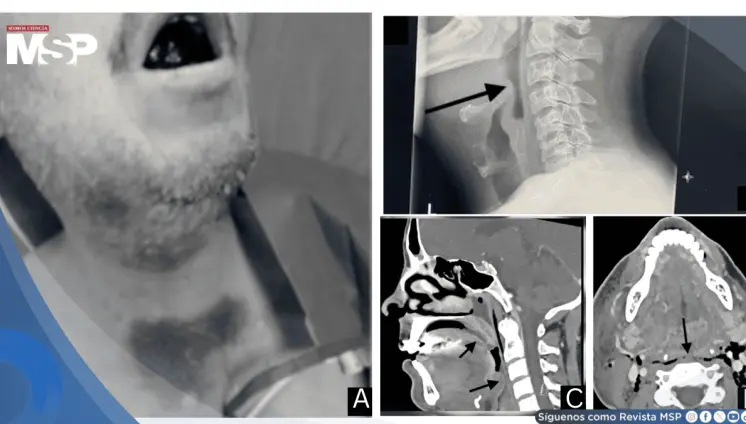

El tabaco cede terreno, pero el virus del papiloma humano gana espacio; especialistas advierten escasez crítica de cirujanos en la isla